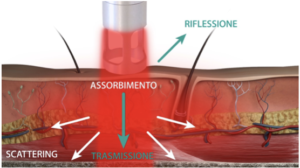

Chiaramente, per fare questo, è necessario che la luce sia in grado di scambiare energia con tessuti biologici e di trasformarla in altre forme di energia biocompatibile, combinando in modo opportuno alcuni parametri caratteristici della luce laser come:

al fine di favorire l’assorbimento, nella maggior quantità possibile, dell’energia creata, evitando al massimo le perdite dovute ad un consumo selettivo dei cromofori, elementi di disturbo che incidono sulla trasmissione della luce e determinano fenomeni di assorbimento, riflessione, rifrazione.